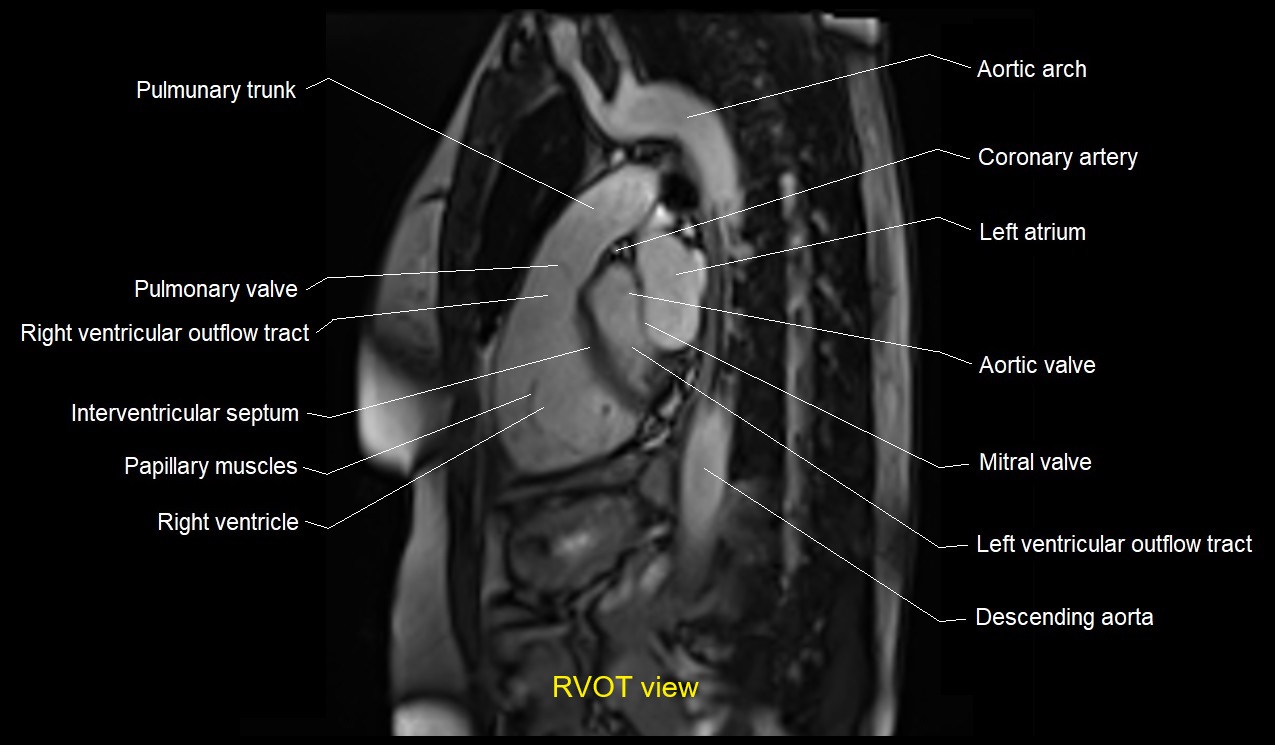

MRI image